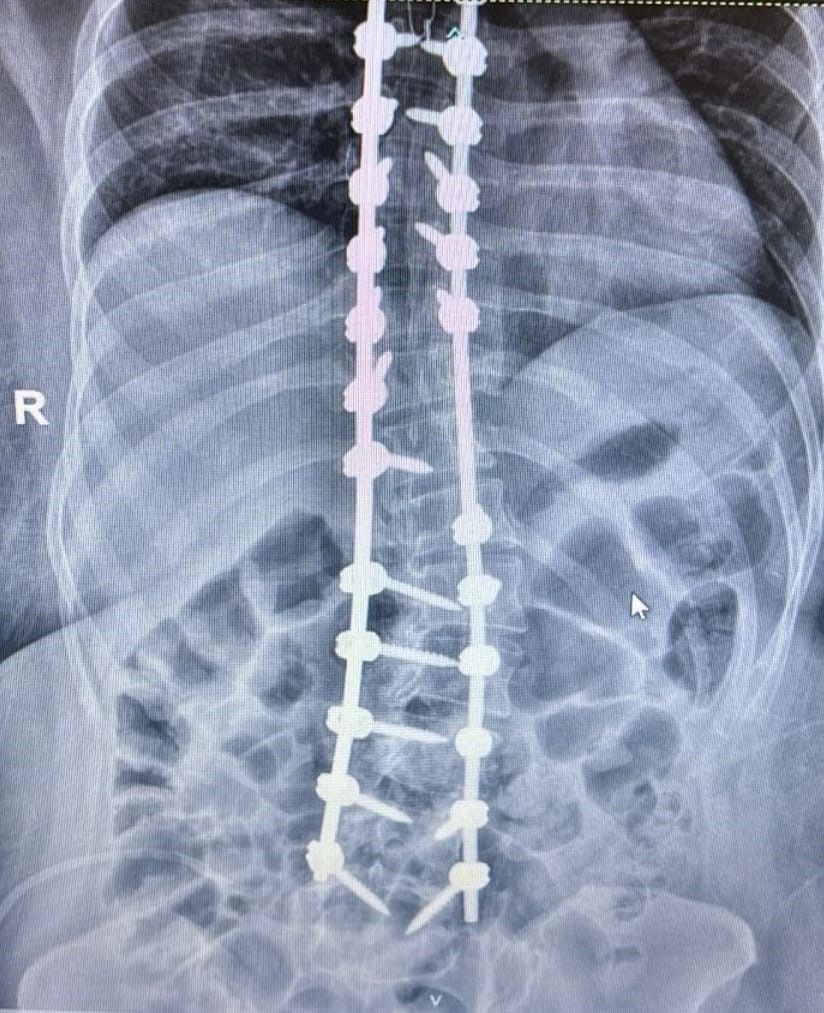

La escoliosis, una alteración en la curvatura de la columna. “Detectarla en etapas tempranas permite evitar su progresión y complicaciones mayores”, señaló.

En paralelo, los avances médicos han transformado las opciones terapéuticas. Procedimientos menos invasivos y tiempos de recuperación más cortos forman parte de la nueva realidad en el tratamiento de estas patologías.

“Hoy podemos ofrecer alternativas más seguras y efectivas, pero cada caso requiere una evaluación individual. No hay soluciones universales”, sostuvo el Dr. Reble.